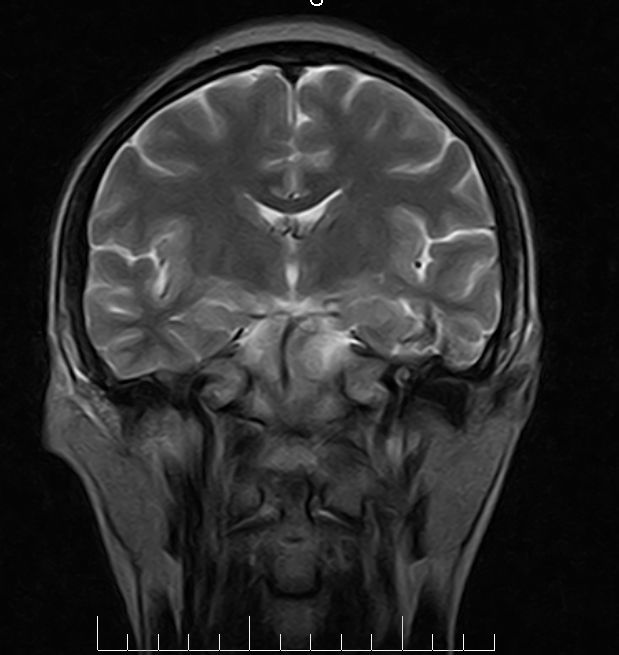

标题: MRI2379:30岁,男,癫痫10年,请各位看一下;CT示:左颞叶钙 [打印本页]

标题: MRI2379:30岁,男,癫痫10年,请各位看一下;CT示:左颞叶钙

左颞叶区见不规则点状混杂信号影

考虑血管畸形

支持2楼 左颞叶区见不规则点状混杂信号影,考虑动静脉畸形。

考虑左侧颞叶脑血管畸形(avm)。

考虑左侧颞叶脑血管畸形(avm)。----t1低等高混杂信号,t2等高信号周边较多流空血管影[冠状位明显],mra左侧大脑中动脉受压,远侧聚集.